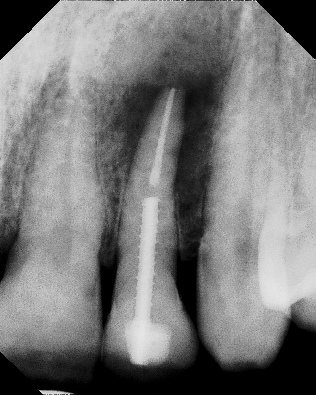

Apicoectomy - Surgical Root Canal Pre-op (post trauma) Coronal segments obturated Apical segments surgically removed 3 years